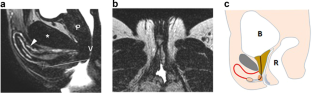

Assigned female at birth with anorgasmia possess a smaller clitoral glans and clitoral components farther from the vagina lumen than women with normal orgasmic function. There are no studies evaluating this correlation in operated transgender women. We evaluated whether differences in MRI measurements of neoclitoris volume and distance between the neoclitoris and the neovagina were correlated with differences in sexual function. We recruited for a prospective survey study 40 operated male to female patients (oMtF) who had undergone genital gender affirming surgery and postoperative pelvic MRI. Individual pelvic MRIs were reviewed by two blinded investigators, the three axes of the neoclitoris were measured and the volume was calculated using the ellipsoid formula. The distance between the neoclitoris and the neovagina was also measured. Sexual functioning was assessed using the Female Sexual Function Index (FSFI) and the operated Male to Female Sexual Function Index (oMtFSFI). Mean scores differences in FSFI, oMtFSFI were examined; associations with clitoral size, location, sexual functioning and demographical variables were investigated as well. The response rate was 55%, 11 MtFs operated with pubic neoclitoris technique (PNT) and 11 with neo-urethroclitoroplasty according to Petrović (NCP). The NCP group presented a neoclitoris mean volume of 1.04 (SD 0.39) cc vs 1.31 (SD 0.78) cc of the other group (p = 0.55). The mean distance between neoclitoris and neovagina was 4.20 (SD 0.57) cm in the PNT group and 2.55 (SD 0.45) in the NCP group (p < 0.001). Patients who had undergone NCP achieved a higher FSFI and oMtFSFI mean Total Score than those operated with the previous technique (FSFI 25.81 SD 3.02 vs 18.62 SD 9.92 p = 0.08; oMtFSFI 37.63 SD 8.28 vs 43.36 SD 13.02 p = 0.23). According to pelvic MRI measurements, this study suggests a correlation between neoclitoral location and oMtF sexual satisfaction.

Vedovo, F., Pavan, N., Bertolotto, M. et al. Neoclitoral location may affect sexual function in transgender women: a preliminary pelvic MRI study. Int J Impot Res 36, 526–530 (2024). https://doi.org/10.1038/s41443-023-00716-2